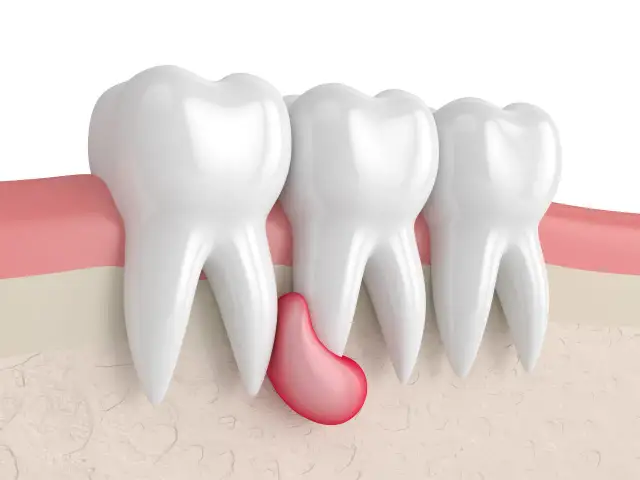

Torbiel pod zębem - Objawy, leczenie, kiedy pilnie do dentysty?

Torbiel pod zębem - dowiedz się, czym jest, jakie daje objawy i powikłania. Sprawdź, kiedy boli, jak diagnozować i leczyć, by uniknąć zagrożeń. Czytaj!